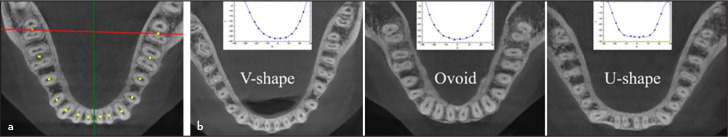

Objective: This study aimed to examine the mandible form features of the mandible, such as inter-second molar width, anteroposterior length, arch perimeter length, arch breadth, corpus height/width in the mandibular second molars (MnSM) region, and arch form, and the relation for the occasion of the 1-rooted/C-shaped.

Methods: The study analyzed cone-beam computed tomography images of 215 male and 215 female Turkish patients to determine the prevalence of 1-rooted and C-shaped MnSM. Mandibular dentoalveolar characteristics of individuals with bilateral (1R-1R group) and unilateral (1R-2R group) 1-rooted MnSM were examined and compared with those with bilateral 2-roots (2R-2R group) MnSM. Statistical tests were performed using Chi-square, one-way ANOVA, Tukey, and binary logistic regression analysis at the 5% significance level.

Results: The prevalence of 1-rooted and 1-rooted/C-shaped MnSM was 12.79% and 9.65%, respectively. Root fusion was more commonly present in females (p<0.05). In the 1R-1R group, the anteroposterior length was shorter than in the 2R-2R group (p<0.05). There was no difference between the groups for other features (p>0.05).

Conclusion: Although the study found a shorter anteroposterior length in the 1R-1R group, no feature was a predictive variable for 1-rooted/C-shaped MnSM.